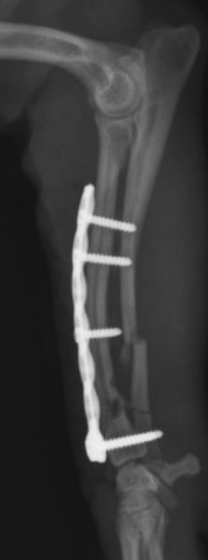

Q

locking plate vs non-locking plate

A

locking plate= screw locks into plate, plate does not touch bone

non-locking= plate and bone need to touch

24

what type of plate can use monocortical screws

locking plate

better to use bicortical screw, because stronger but not needed

plate should be same length as bone and as close to bone as possible, but does not have to touch to work

25

how to place locking plate

fracture must be reduced before placement very specific on how screws have to be placed place standard screw first (bone next to plate)

26

advantages of locking plates

no need to contour plate to bone- does not need to touch to work can use monocortical screws less likely to fail in weak or thin bones